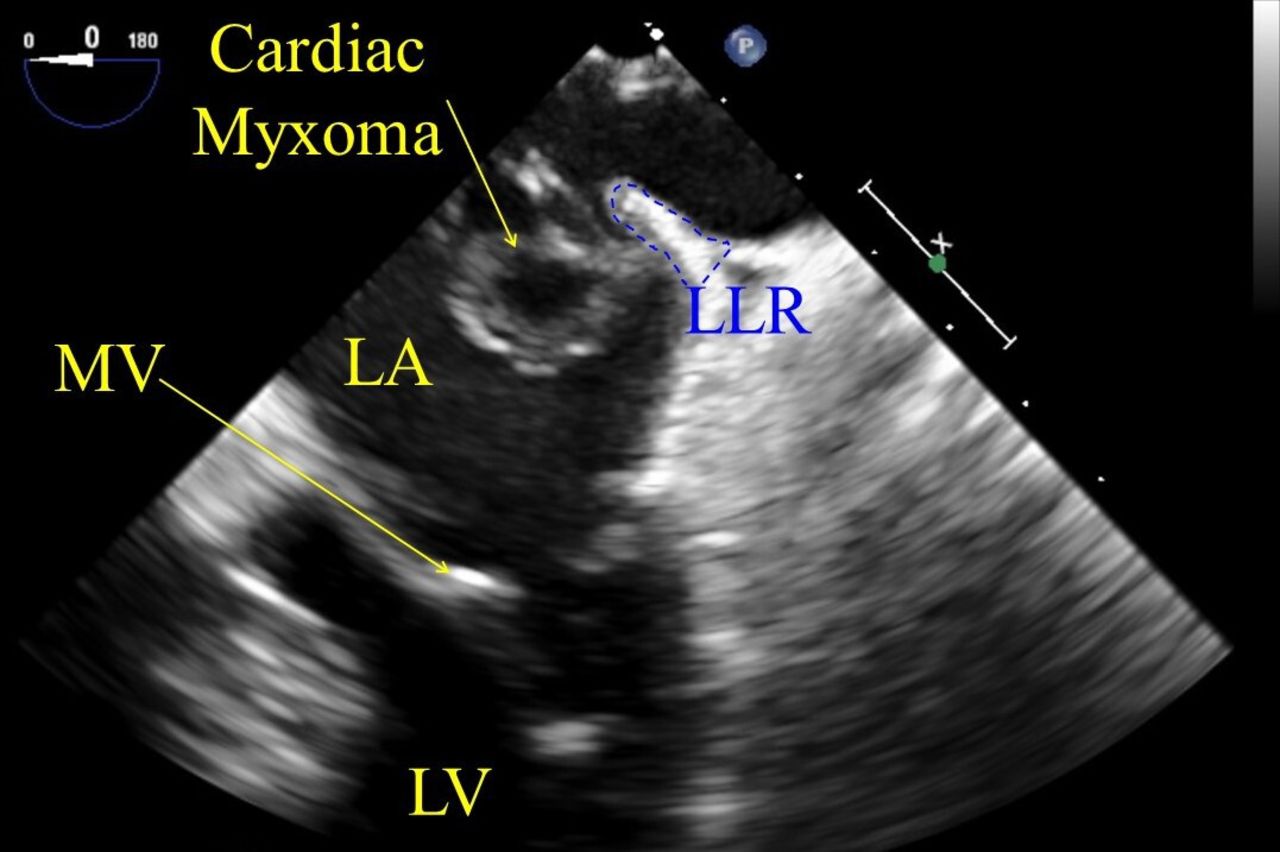

УЗИ выявляет следующие анатомические признаки:

В серошкальном режиме определяется округлое или овальное образование в полости предсердия, чаще с прикреплением к межпредсердной перегородке в области овальной ямки.

Эхогенность опухоли варьирует: она может быть гипоэхогенной с участками неоднородности или гиперэхогенной при наличии кальцинатов.

В режиме цветного допплера визуализируется турбулентный поток крови вокруг подвижного образования, особенно при пролабировании через клапан.

На трансторакальном УЗИ определяется подвижность миксомы в диастолу и систолу, что важно для выявления риска блокады клапанного отверстия.

В трансэзофагеальном режиме визуализируется место прикрепления и возможные участки некроза внутри опухоли.